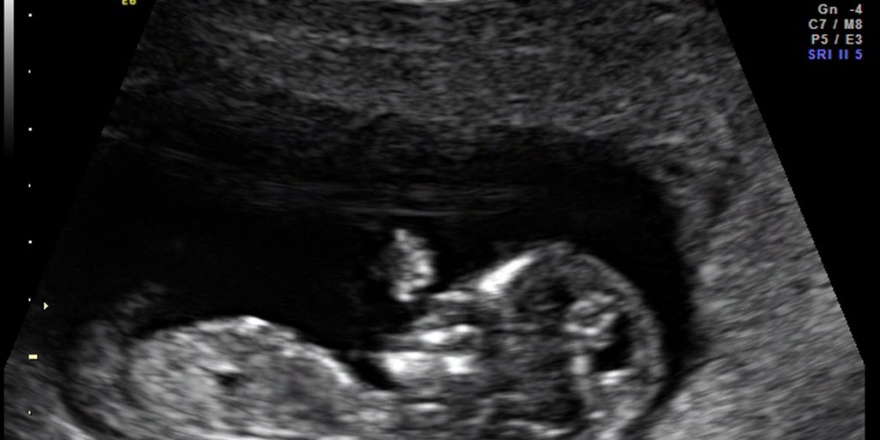

Das Ersttrimester-Screening wurde in den letzten Jahren entwickelt und intensiv geprüft. Es ist allerdings nur in dem Zeitfenster zwischen der 11. Und 14. SSW sinnvoll. Denn genau in diesem Zeitraum ist die Nackenregion des Embryos ein guter „Anzeiger“ für Chromosomenstörungen oder bestimmte Herz-Lungen-Erkrankungen. In der Nackenregion erscheint im Ultraschallbild eine Art Blase, die flüssigkeitsgefüllt und daher durchsichtig ist. Es ist der Raum zwischen Haut und Weichteilgewebe, der wegen der Durchsichtigkeit „Nackentransparenz“ oder „Nackenfalte“ genannt wird.

Ein Experte kann die Dicke der Nackentransparenz vermessen, mit der Gesamtlänge des Embryos vergleichen und daraus Rückschlüsse ziehen. Eine geringe Nackentransparenz ist als normal anzusehen. Für kurze Zeit aber gibt es einen Zusammenhang zwischen der Nackentransparenz und Entwicklungsstörungen: Je breiter diese durchsichtige Blase, desto größer das statistische Risiko für eine Chromosomenstörung, etwa das Down-Syndrom.